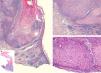

Complete excision of the lesion was performed and histopathology revealed an epidermal lesion of endophytic growth formed by mature keratinocytes in the central axis and basaloid cells in the periphery (Fig. 2). There were also intralesional corneal cysts surrounded by a dermal inflammatory infiltrate of lymphocytic predominance. These findings confirmed the diagnosis of inverted follicular keratosis (IFK).